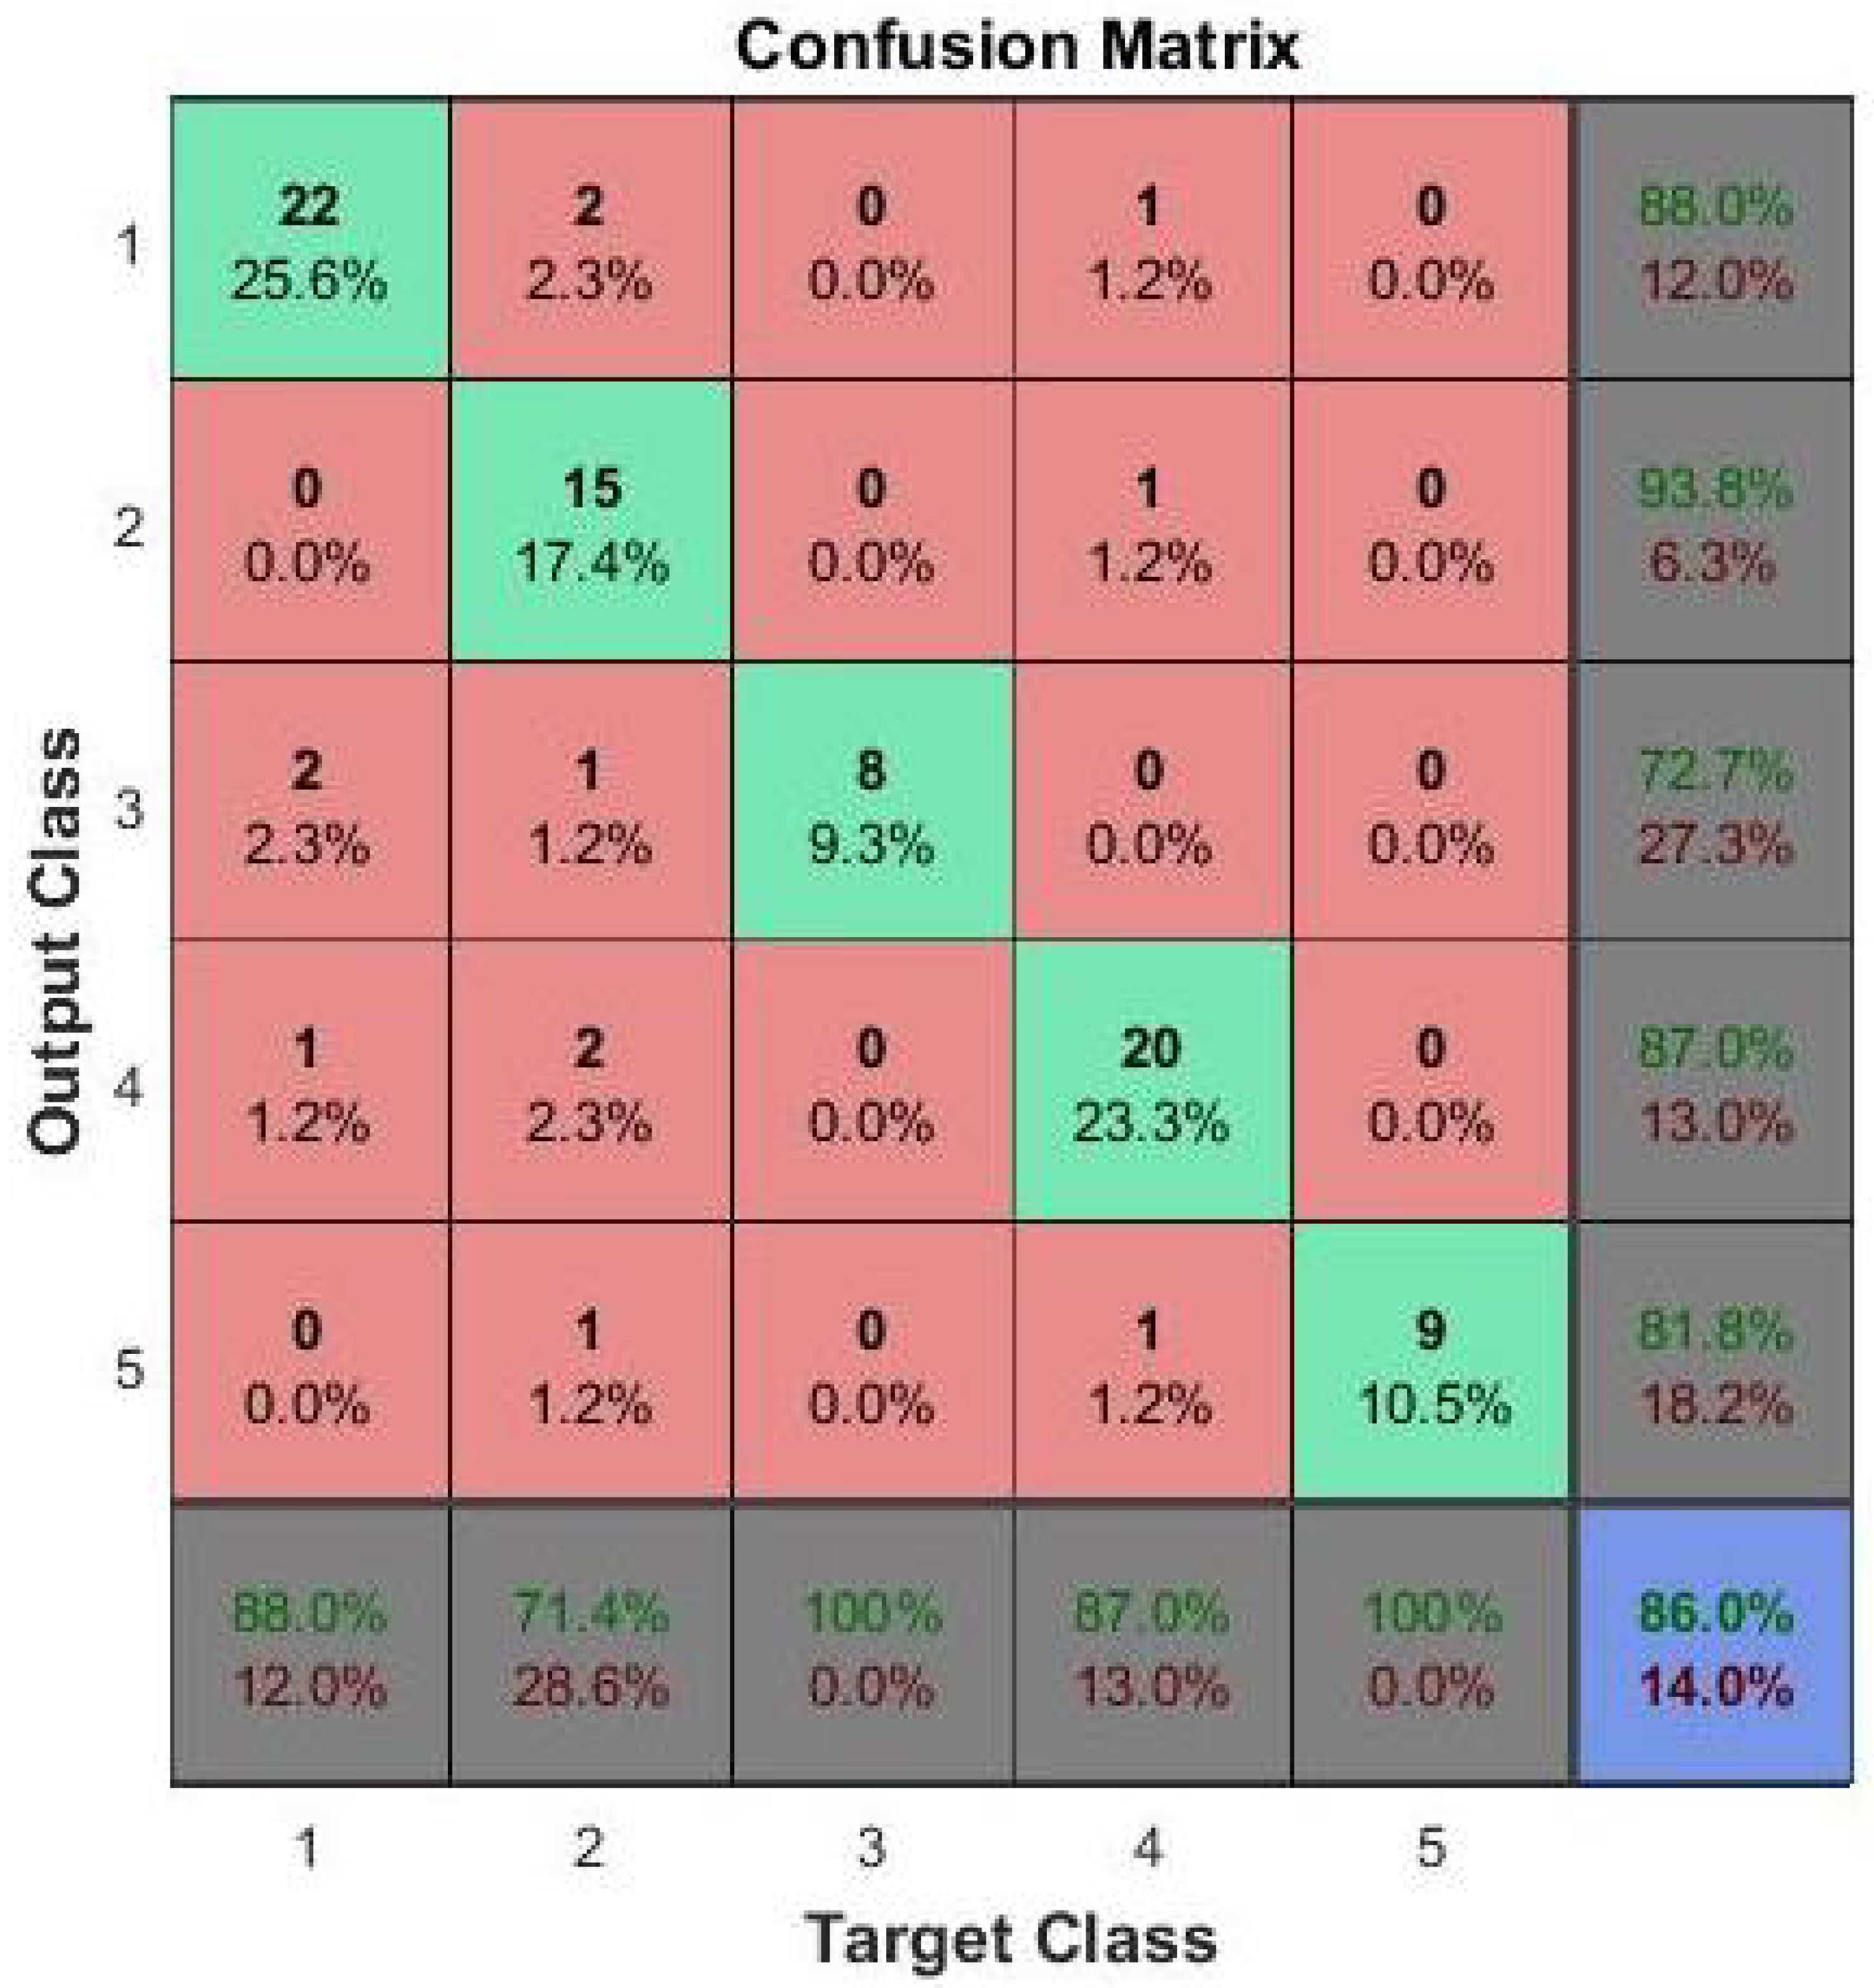

3.5. Grading Stage

| Metrics | FCNN | Two-Level SVM Classifier |

|---|---|---|

| Accuracy (%) | 86.0 ± 1.0 | 80.0 ± 1.0 |